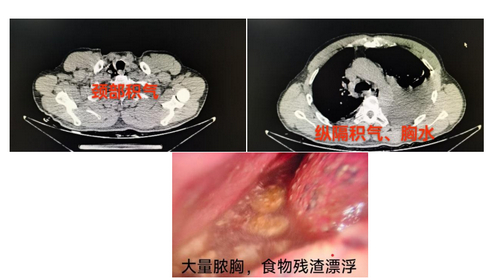

2026年除夕夜,当万家团圆之时,安岳县中医医院骨科收治了一名饮酒后呕吐、背痛的患者。经初步判断,排除骨科疾病,请外一科急会诊,确诊为被称作节假日里“隐形杀手”的Boerhaave综合征——即食管自发性破裂。经家属同意后急诊手术治疗。然而,患者被送达手术室时,病情已进一步恶化:出现严重感染、休克、呼吸衰竭,术中见胸腔内积脓达2000毫升,并漂浮着大量食物残渣。